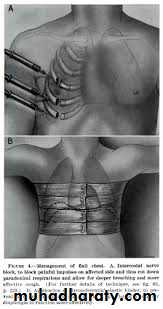

Flail chest

Flail chest x ray

Management of flail chest